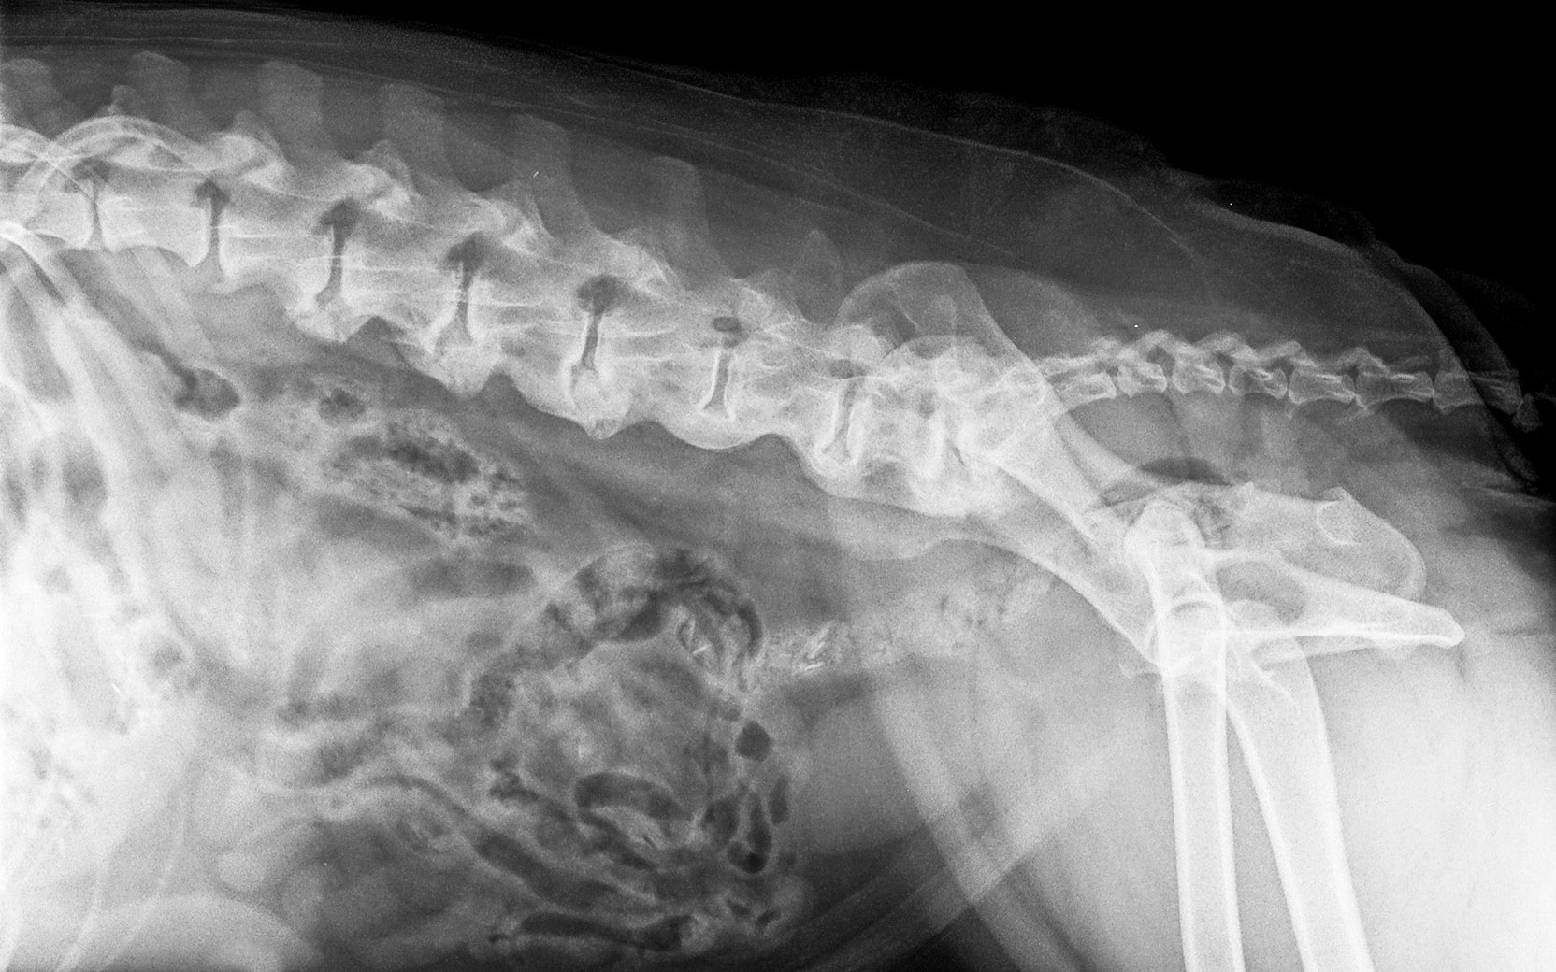

Die Spondylose ist eine Erkrankung mit Deformierung der Wirbelsäule. Es kommt zu spornschnabel- oder brückenförmigen, knöchernen Zubildungen an der Unterseite, der Seite oder selten auch der Oberseite der Wirbelkörper. Betroffen sind vor allem große, schwere Hunderassen wie der Deutsche Boxer, Deutsche Schäferhund, Rottweiler, Bernhardiner und Retriever sowie Hunde mit langem Rücken, wie dem Dackel. Die Erkrankung kann jedoch auch bei allen anderen Hunderassen vorkommen.

Die meisten Spondylosen sind Zufallsbefunde, die während einer aus einem anderem Grund durchgeführten Röntgenuntersuchung auffallen. Im Röntgenbild kann dein/e Tierärzt:in die typischen Veränderungen genau lokalisieren und das Ausmaß der Zubildung bestimmen.